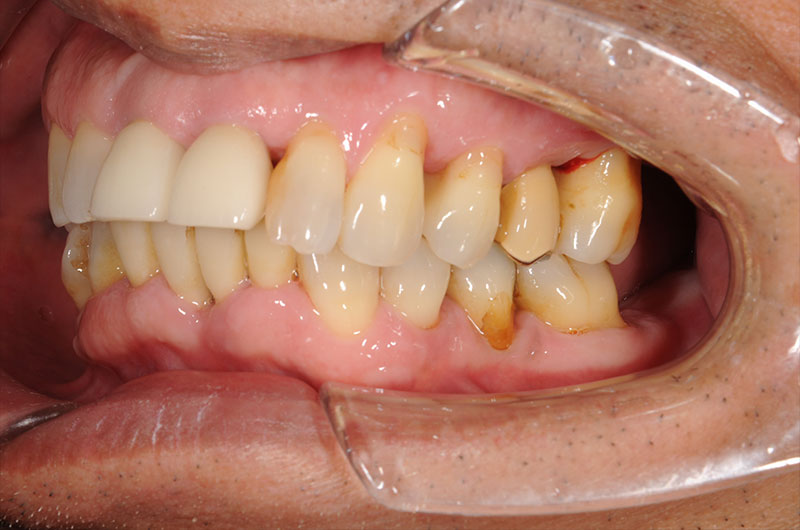

インプラント治療 ②

before

after

• 年齢

44歳

• 性別

女性

• 治療期間

24ヵ月

• 費用

‭4,252,500円